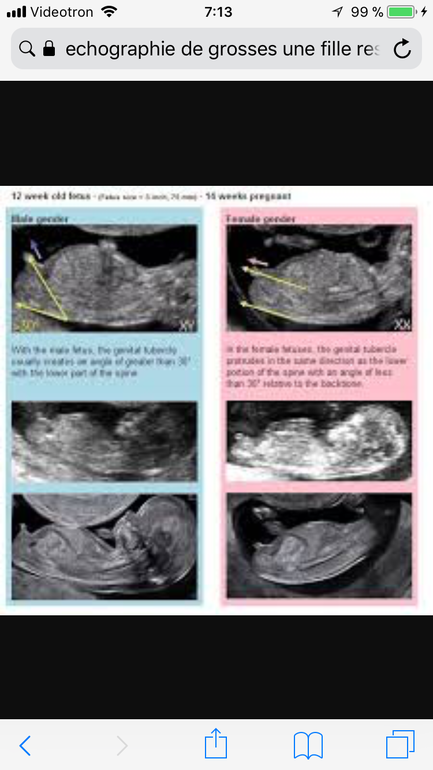

Вот покамись посмотрите мальчик или девочка, сайт на французском но там и так все понятно

http://www.mysweetlittlebaby.fr/2016/03/echographie-comment-connaitre-le-sexe-du-bebe-fille-ou-garcon-je-vous-aide.html

У девочек горизонтально лежит,а у мальчишек" плавает". Как собсвенно в вашем случае☺